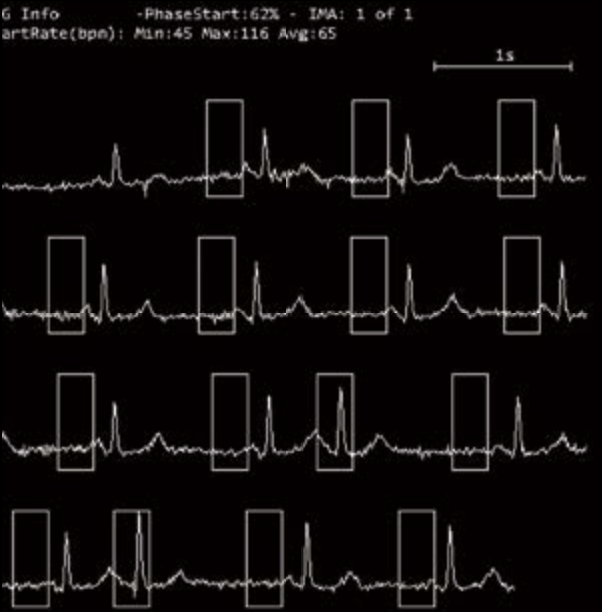

- Интеллектуальная платформа коронарной визуализации мгновенно замораживает сердце и отображает информацию высокого разрешения о сердечно-сосудистых структурах, стентах, кальцификации и бляшках с помощью уникальной интеллектуальной системы управления и алгоритмов коронарной реваскуляризации SinoVision.

- Модуляционная стробировка в реальном времени

- Система модуляции с бегущим контролем

- Редактирование ЭКГ

- Автоматический захват фазы

- Отображение данных о дыхательных волнах

- Управление стробированием на основе модуляции в реальном времени - Система управления модуляцией синхронизации - Редактирование ЭКГ - Автоматический захват фазы - Отображение данных дыхательной волны - Встроенная система управления синхронизацией - Интеллектуальная аналитическая платформа